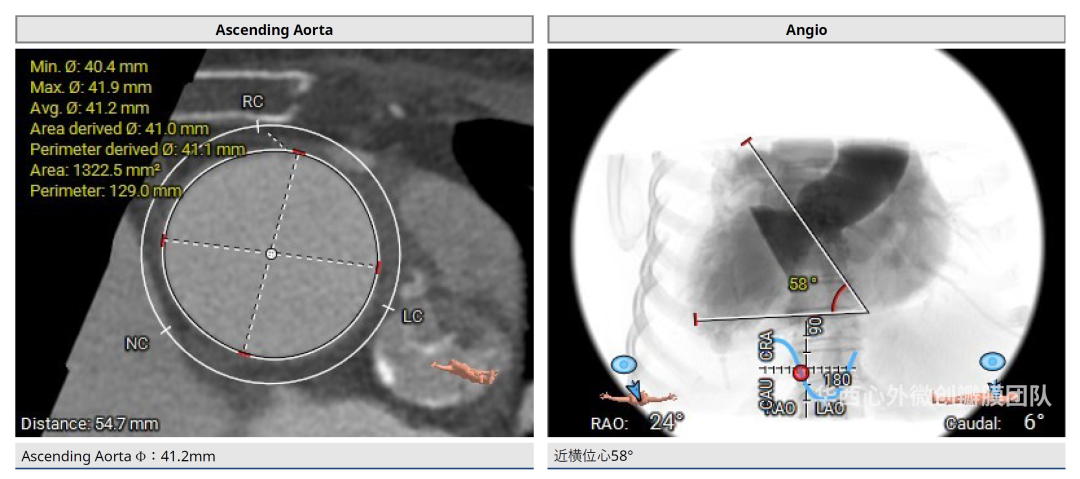

术前CT评估

患者镜面右位心,主动脉瓣二叶式,Type 0-lat型,瓣环面积410.3mm²,面积折算直径22.9mm,左冠开口高度14.1mm,右冠开口高度14.7mm,瓣叶增厚,重度钙化,主要分布于瓣叶游离缘,瓣环、流出道、STJ未见明显钙化累及,升主动脉可见扩张,近横位心58°。患者外周血管条件尚可,胸主动脉迂曲、成角90°,未见明显钙化。